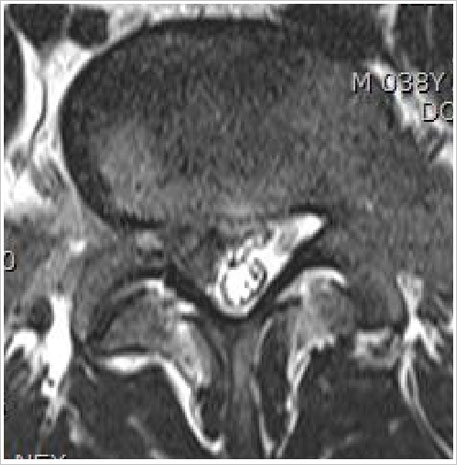

ôÃß¿¡ ÀÖ´Â µð½ºÅ©, ´Ù¸¥¸»·Î´Â Ãß°£ÆÇÀº ôÃß»À »çÀÌ¿¡¼ Äí¼Ç

¿ªÇÒÀ» ÇÏ´Â ¾ãÀº Ÿ¿øÇü ±¸Á¶¹°ÀÔ´Ï´Ù. °¢°¢ÀÇ µð½ºÅ©´Â ºÎµå·¯¿î Á©¸® »óÅÂÀÇ ¼öÇÙÀ» ¼¶À¯Áú

²®µ¥±â°¡ µÑ·¯ ½Î°í ÀÖ´Â ¸ð¾çÀÔ´Ï´Ù. ÀÌ ±¸Á¶´Â µð½ºÅ©°¡ ôÃß»À »çÀÌÀÇ °ø°£À» À¯ÁöÇÒ

¸¸Å ´Ü´ÜÇϸ鼵µ ôÃß°¡ ±¸ºÎ¸®°í ȸÀüÇÏ´Â µ¿ÀÛÀ» ÇÒ ¶§ ¿òÁ÷ÀÓÀ» °¡´ÉÇÏ°Ô ÇÕ´Ï´Ù. |